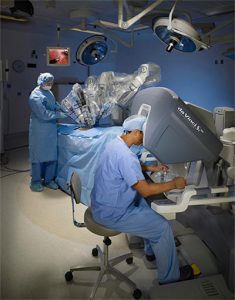

அறுவை சிகிச்சை துறையில் டாவின்சி சி.எச்.டி என்ற கருவி அறுவை சிகிச்சை தானியக்க கருவிகளை உருவாக்கியுள்ளது. உடல் உள் உறுப்புகளுக்கு சிகிச்சை அளிப்பதற்கு மீச்சிறு அளவு துளைகள் மூலம்ரோபோக்களை அனுப்பி வைத்து மருத்துவர்கள் உள் உறுப்புகளின் நிலையை துல்லியமாக கண்டு கொள்வதை சாத்தியமாக்குகிறது.